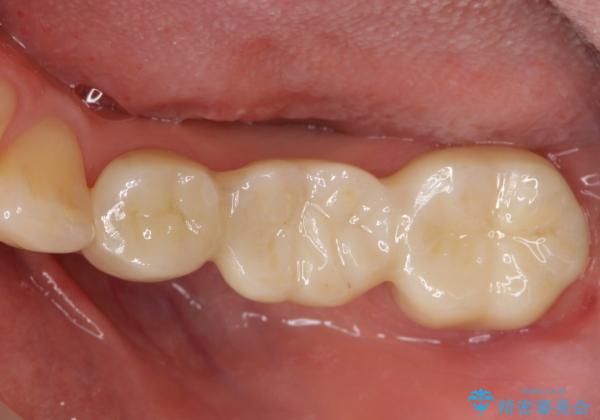

- 左下の銀歯の状態が悪く抜歯してブリッジにした患者様です。

抜歯してからブリッジの仮歯をすぐ入れるため、歯がない期間はほとんどありません。

- 36.3万円 (ジルコニアクラウン 10万円×3、仮歯1万円×3)費用は治療当時の料金となります

途中全体矯正をはさみ、根の向きが並行になった状態でブリッジを入れることができました。